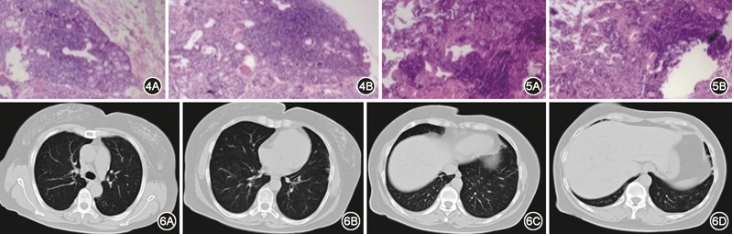

2024-01-15在局部麻醉下行支气管镜检查:双肺各叶段支气管内见较多白色分泌物,管腔黏膜光滑,未见新生物,于双肺下叶行支气管肺泡灌洗、刷检,送检病原学:支气管镜刷检物及灌洗液均未查到细菌、真菌及抗酸杆菌,灌洗液病原体靶向测序tNGS、GeneXpert均阴性。于左肺下叶外后基底段行TBLB提示黏膜慢性炎症,未查见肿瘤细胞。2024-01-18行唇腺活检,病理可见淋巴细胞浸润灶,4个/4 mm2,淋巴细胞数≥50个(图4)。

患者青年女性,口干症状持续3个月,伴吞咽困难,血清抗SSA、SSB抗体阳性,唇腺灶性淋巴细胞浸润,且灶性指数>1个灶/4 mm2,符合2016年美国学会与欧洲联盟原发性干燥综合征(primary Sjögren′s syndrome,pSS)分类标准[1],pSS诊断明确。2024-01-25行胸腔镜下右肺下叶肺活检术,术后病理示:肺泡隔内间质淋巴细胞浸润为主,局部纤维化,伴有肺泡上皮增生,呈片状或细支气管中心分布(图5)。

最终诊断:原发性干燥综合征并非特异性间质性肺炎。治疗上给予甲泼尼龙(40 mg/次,静脉推注,1次/d),羟氯喹(200 mg/次,口服,2次/d),2024-02-10复查胸部CT:双肺病灶较前基本吸收(图6)。

图4 2024年1月18日唇腺活检组织病理:唇腺组织内见灶状淋巴细胞浸润,唇腺腺泡轻度萎缩,间质少量脂肪组织填充,间质纤维化不明显,小叶内导管轻微扩张;灶性指数为4;Chisholm组织病理分度:Ⅳ度 HE 低倍放大

图5 2024年1月25日(右肺下叶)肺活检病理:间质伴大量以淋巴细胞为主的慢性炎细胞浸润,局部纤维结缔组织增生,可见少量增生的平滑肌组织;周围肺泡上皮增生,未见明显异型性 HE 低倍放大

图6 2024年2月10日胸部CT(轴位)双肺少许条索状影,双肺反晕征病灶吸收